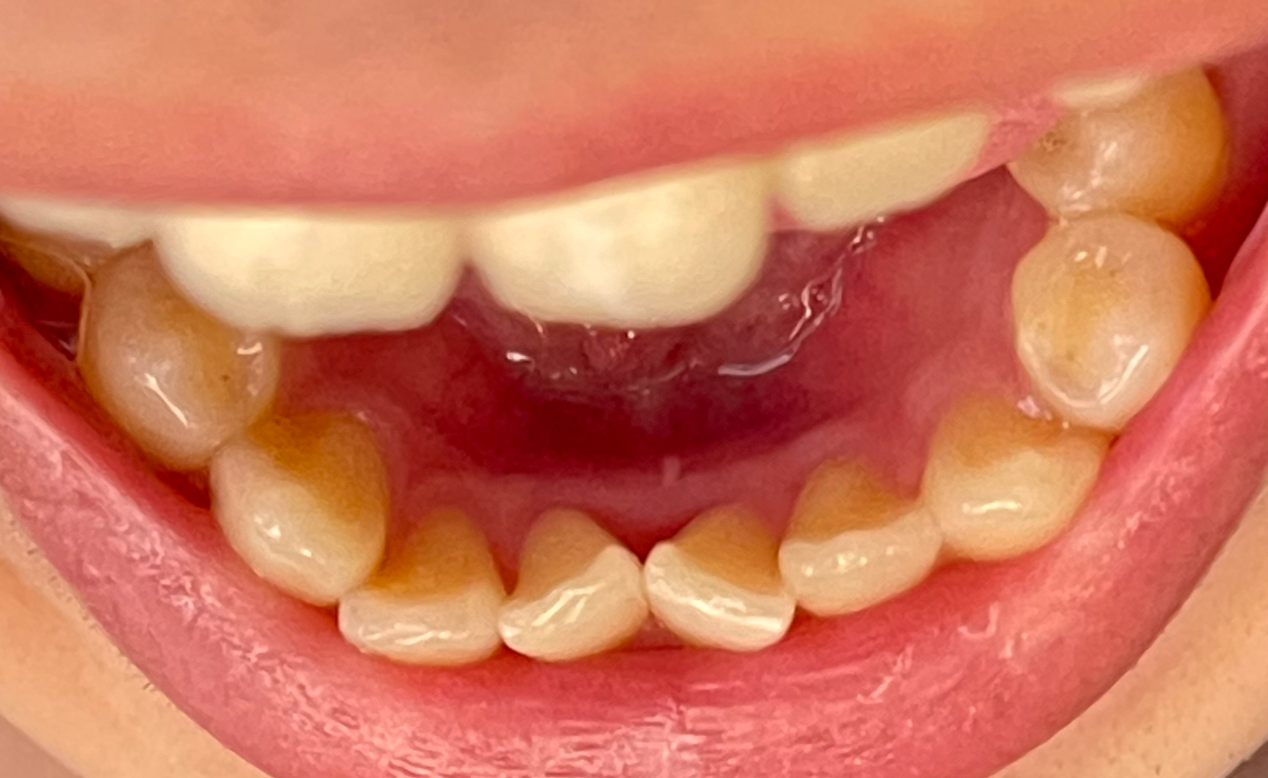

이후로 자세히 안 보고 살았는데 현재 모습입니다. 좀 누르스름 하긴 하지만 치석은 크게 쌓인 거 같지는 않네요.